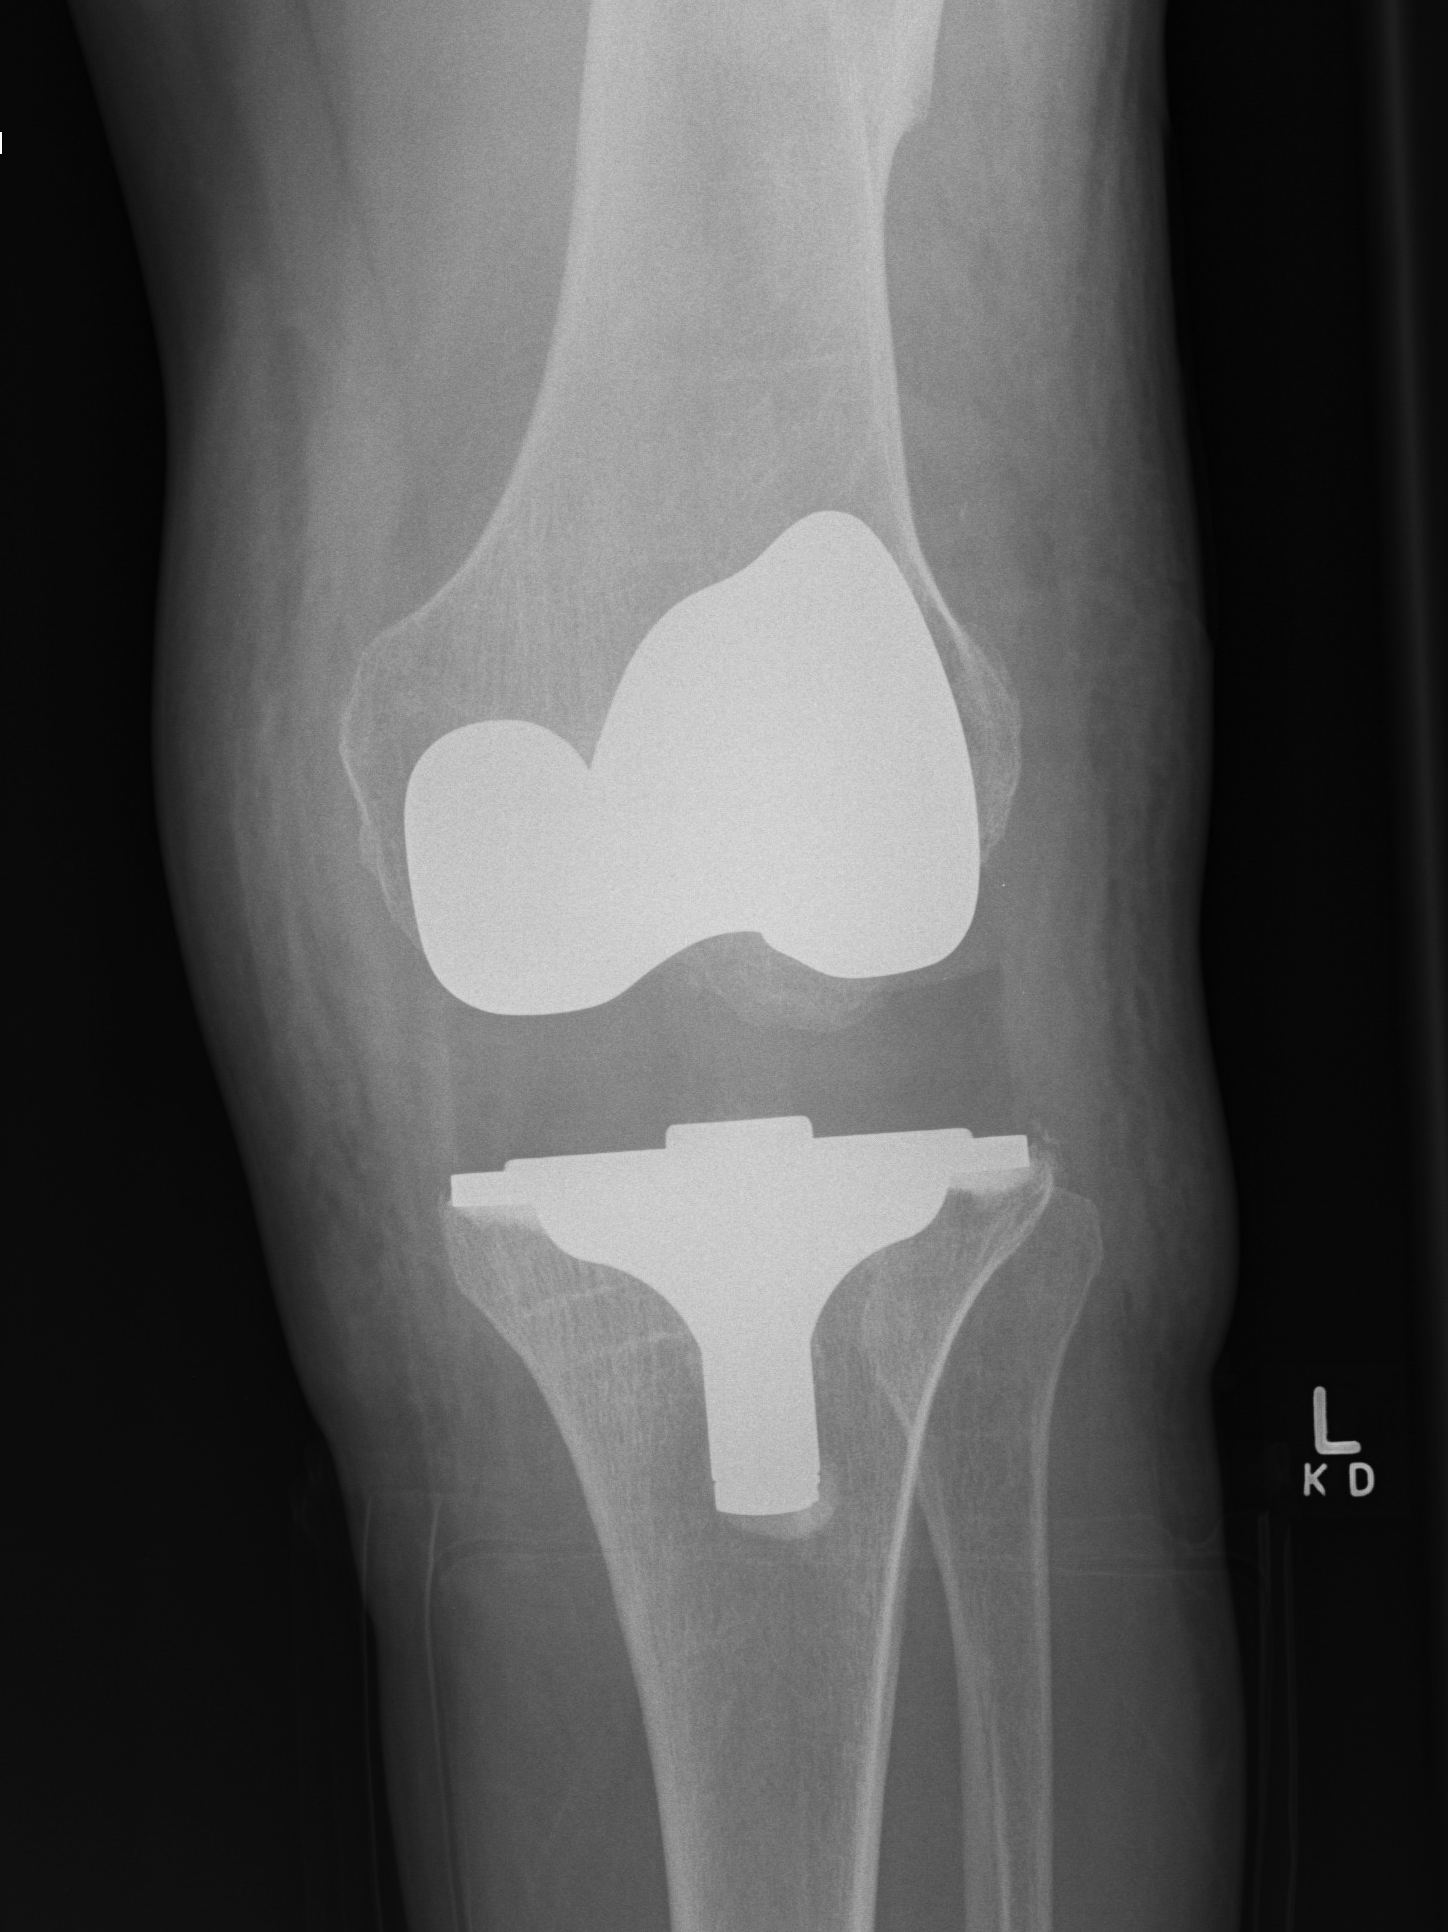

2. Varus Valgus Instability

Varus-Valgus instability

Causes